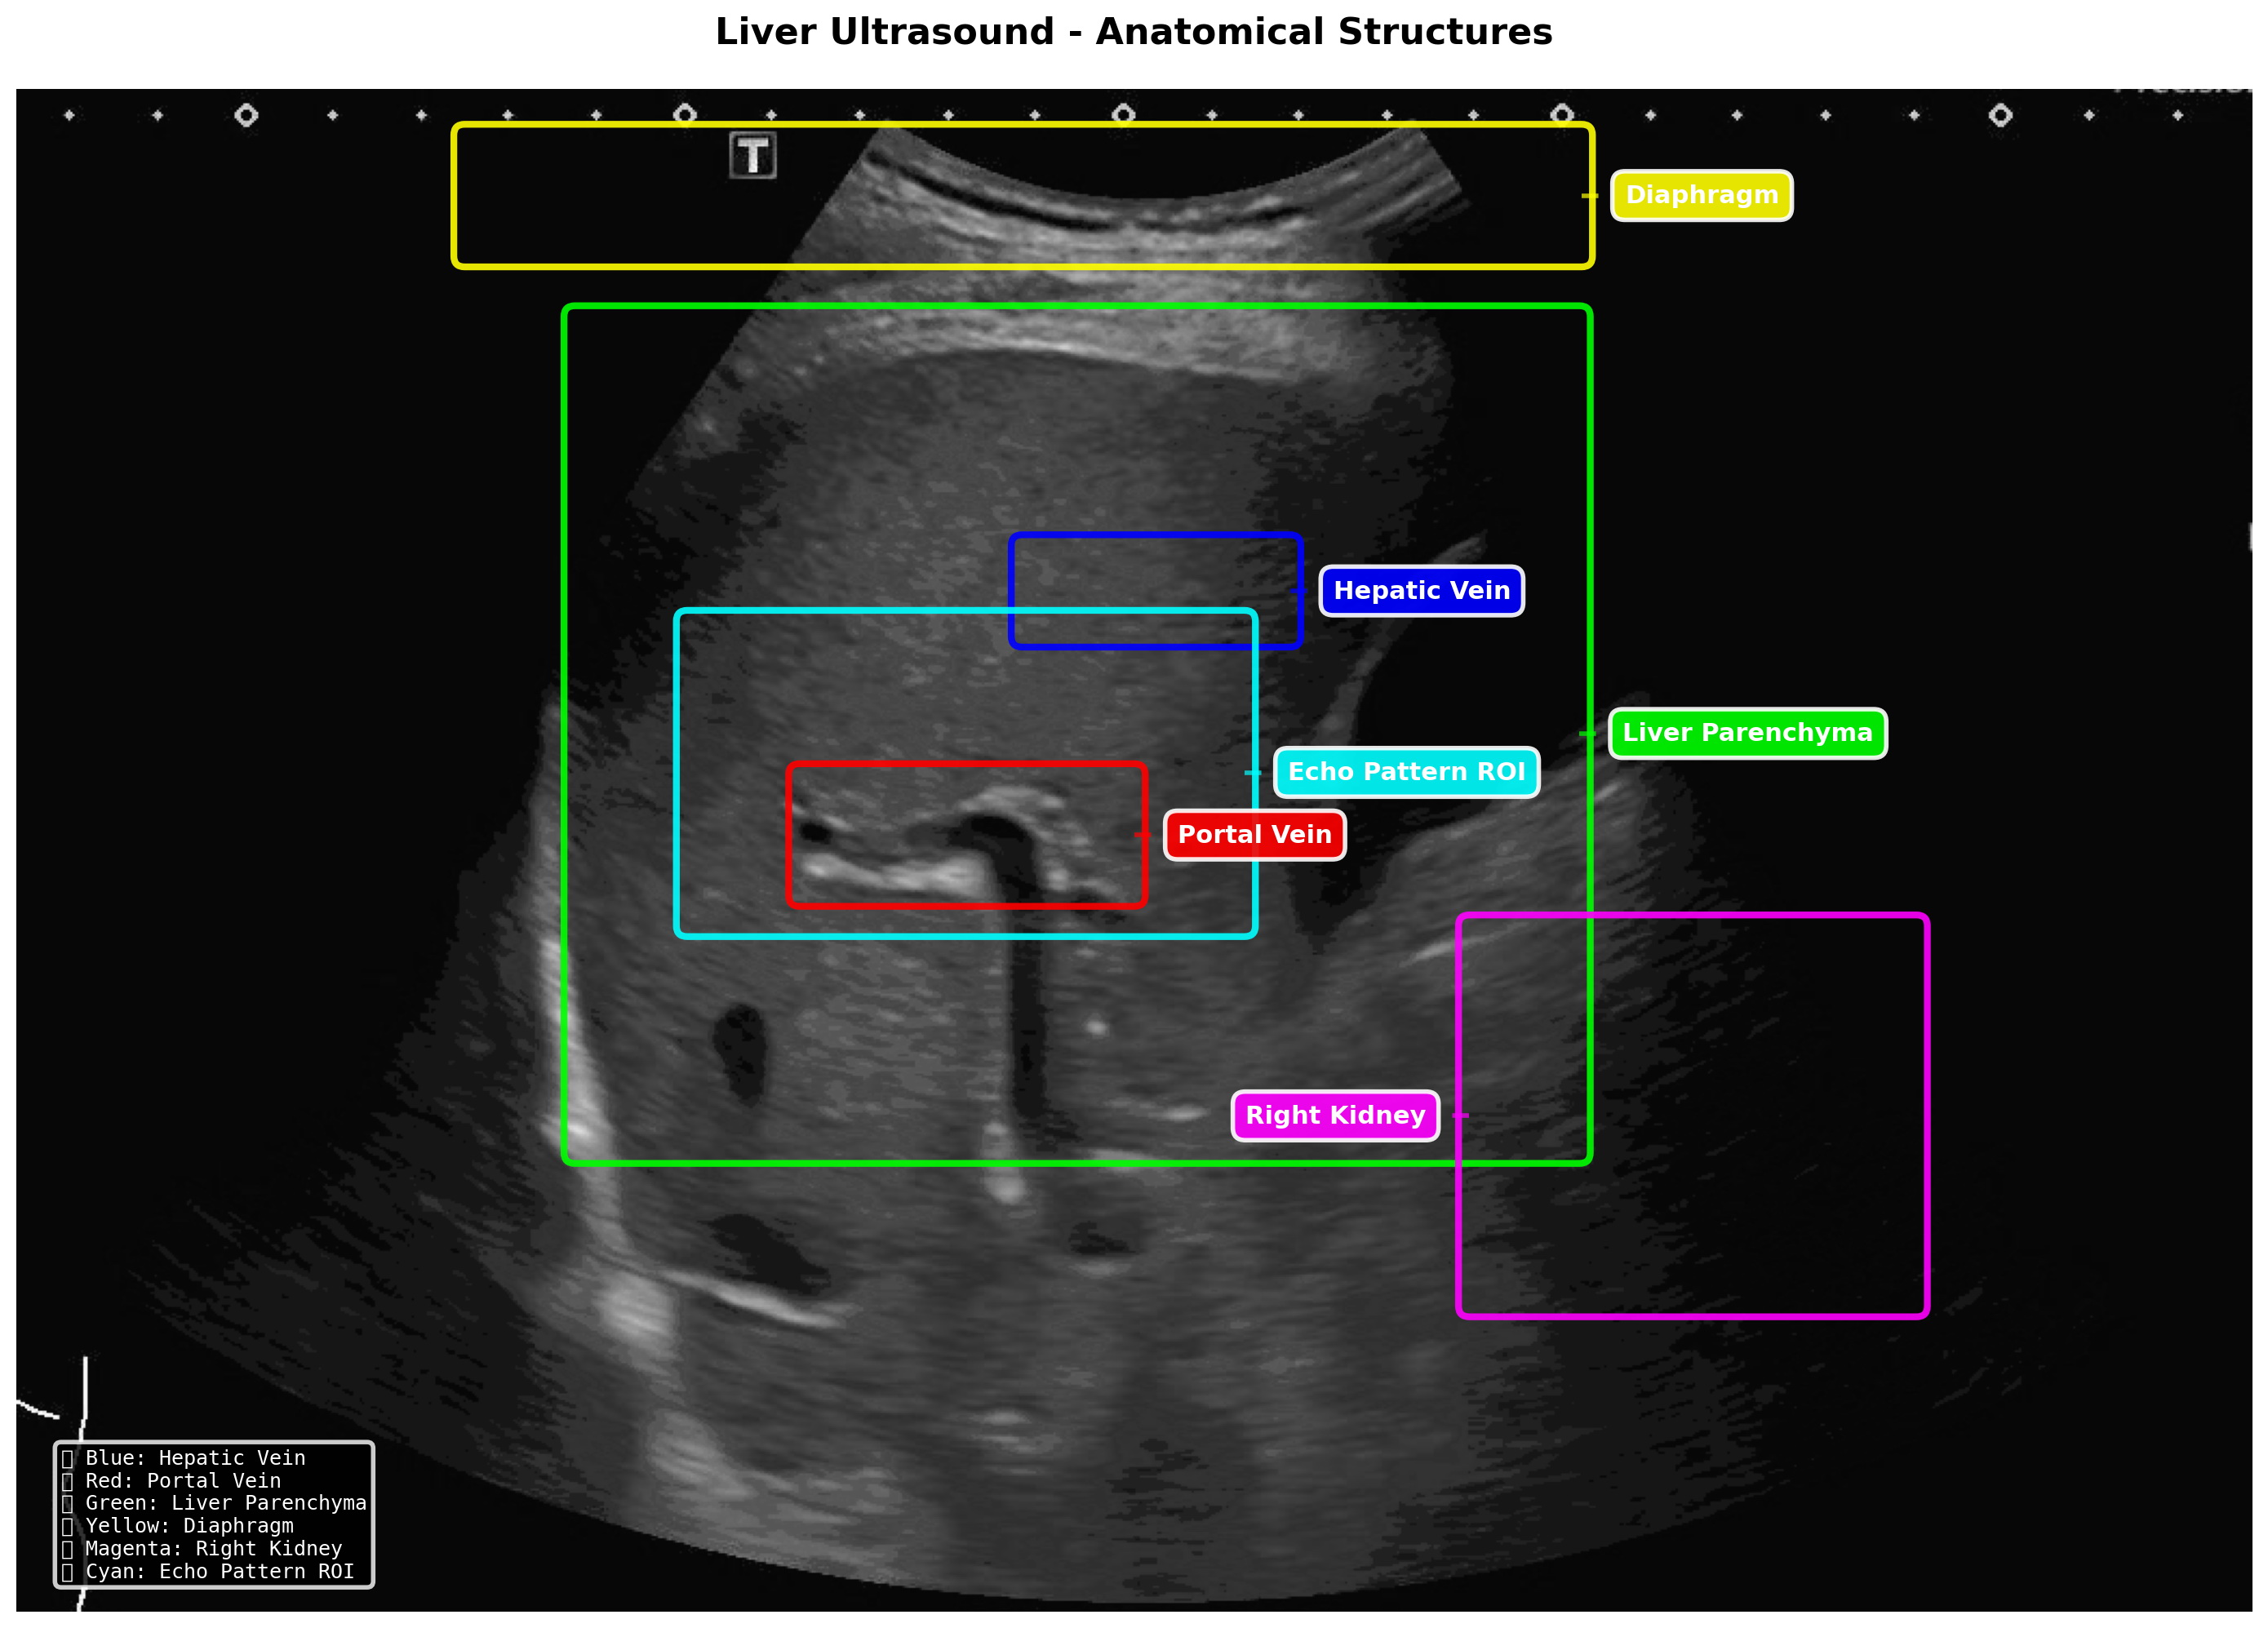

SmartLiva ทำงานเหมือน “อัปเกรด” จากภาพอัลตราซาวด์ขาวดำธรรมดาให้กลายเป็นผลวินิจฉัยที่อ่านง่ายและแม่นยำ โดยแพทย์อัปโหลดภาพผ่านเว็บได้ทั้งบนคอมพิวเตอร์หรือแท็บเล็ต จากนั้นระบบจะช่วยปรับภาพให้ชัดขึ้น คัดเฉพาะบริเวณเนื้อตับที่ต้องวิเคราะห์ และทำให้ภาพดูเข้าใจง่ายขึ้นด้วยการไฮไลต์เป็นสี (เช่น ตับเป็นสีแดง ไขมันเป็นสีเหลือง) เพื่อให้เห็นความผิดปกติได้ทันที โดย AI จะทำการประเมิน 3 เรื่องพร้อมกัน คือ ประเมินระดับพังผืด/ความแข็งของตับ (F0–F4) ตรวจหาความผิดปกติของเนื้อเยื่ออย่างถุงน้ำหรือมะเร็งตับ และตรวจหาพยาธิใบไม้ตับ ซึ่งตัว AI จะทำการประมวล วิเคราะห์ และสรุปผลออกมาเป็นรายงานพร้อมภาพประกอบและคำอธิบายที่คนทั่วไปเข้าใจได้ โดย AI ทั้งหมดถูกฝึกฝน (Train) ด้วยฐานข้อมูลภาพอัลตราซาวด์กว่า 50000 ภาพ จากโรงพยาบาลชั้นนำ อย่างโรงพยาบาลขอนแก่น โรงพยาบาลจุฬาลงกรณ์ และโรงพยาบาลรามาธิบดี